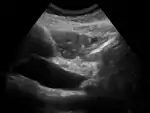

Відрізнити клініко-анатомічні форми холестазу одне від одного за допомогою клінічних проявів і лабораторних показників важко, тому велике значення має ультразвукова діагностика і комп'ютерна томографія. У деяких випадках застосовують особливе дослідження — ретроградну холедохопанкреатографію, при якій за допомогою фіброгастродуоденоскопа вводять всередину жовчних шляхів рентгенконтрастну суміш барію, після чого за допомогою рентгенівської техніки отримують знімки, по яких судять про виділення або затримку барію в жовчних ходах, що є особлив цінним у випадках виникнення холестазу через пухлину голівки підшлункової залози. Рідше використовують черезшкірну транспечінкову холедохопанкреатографію.